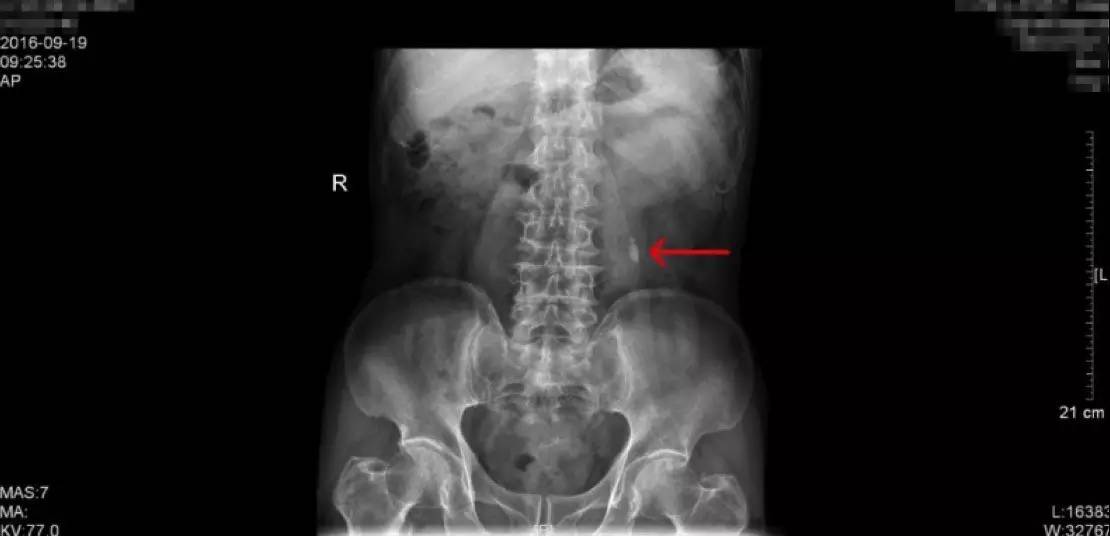

KUB检查报告:结石最大为1.2cm

KUB这一检查是泌尿系结石的常规检查之一,学名称为泌尿系平片,一般是指患者在经过肠道准备后(前一天服用泻药,让肠道内容物排出,第二天禁食,以减少肠道内容物对影像的干扰),在X线透视下摄片,涵盖整个泌尿系统,包括肾、输尿管、膀胱区域,观察这一区域有无阳性结石(酸性结石,尤其纯的酸性结石在X下无法显现,我们称为阴性结石,这一检查就无法看到,但比较少)。这一患者的KUB检查片子如上,可以看到,阳性结石表现为白色的强化,就是片子中红色箭头所指的地方,一般患者手术后也要拍一张KUB,可以和术前的检查相对比,从而直观的确认手术的效果。